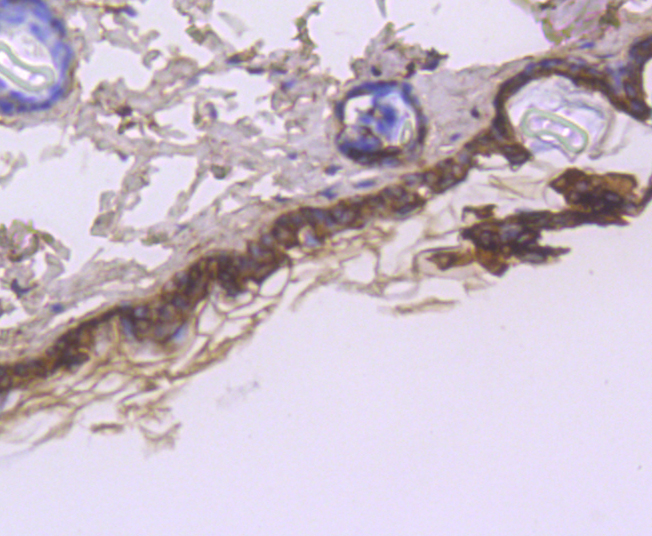

Immunohistochemical analysis of paraffin-embedded mouse skin tissue using anti-Cytokeratin 1 antibody. Counter stained with hematoxylin.